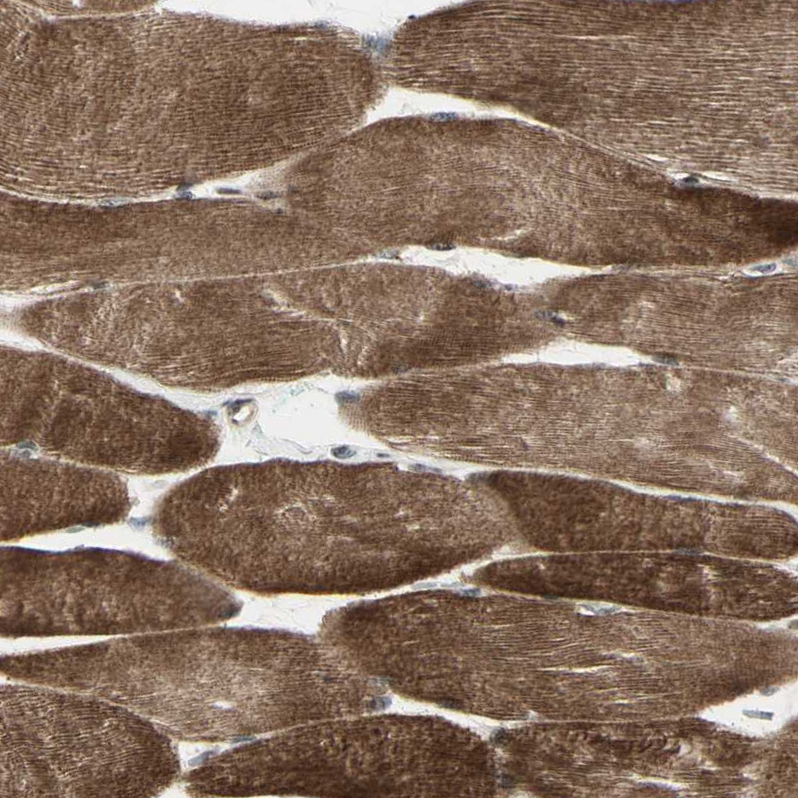

Immunohistochemical staining of human skeletal muscle shows strong cytoplasmic positivity in myocytes.